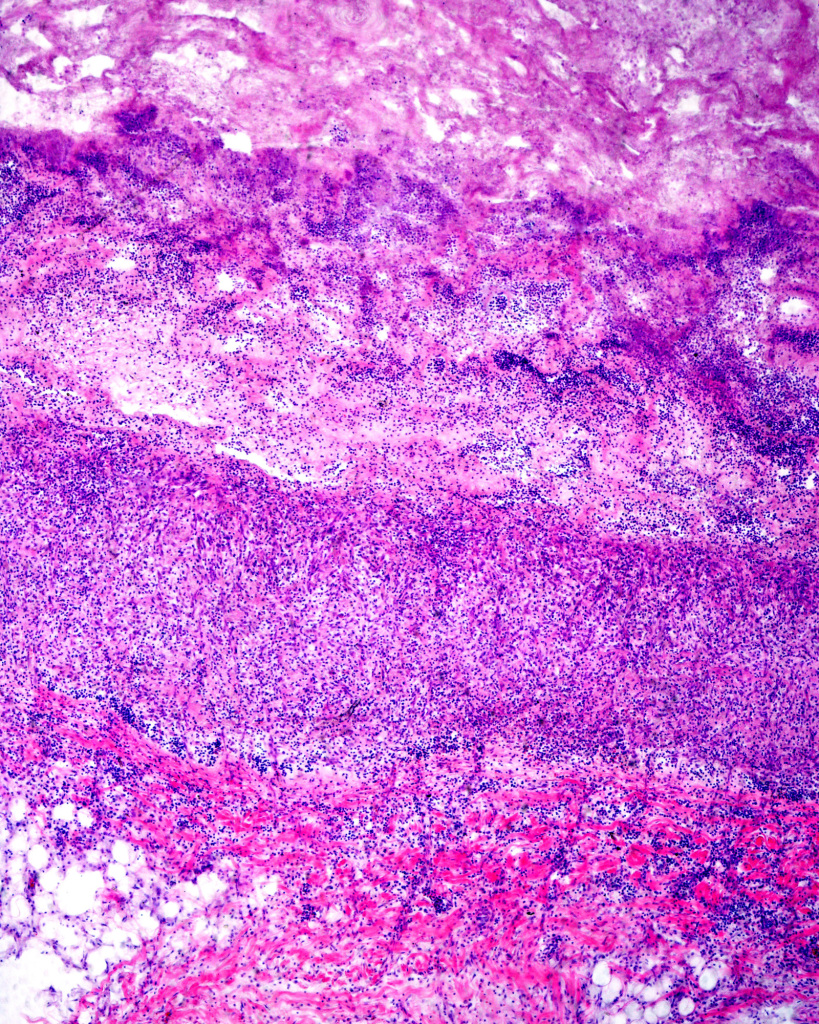

Our medical studies confirmed our interest in histology.